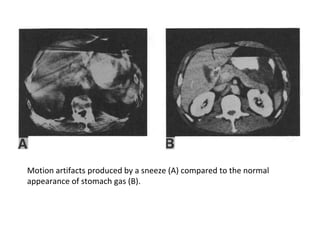

MOTION ARTIFACT

• Reconstruction can not make corrections as

motion is random and unpredictable

• Object in motion is displayed as a streak in the

direction of motion and densities of pixels are

averaged in the motion area

• Intensity of streak artefact depends upon the

density of object in motion

• Motion of objects that have densities much

different from their surroundings (air, metal)

produces more intense artefacts.

Motion artifacts produced by a sneeze (A) compared to the normal

appearance of stomach gas (B).